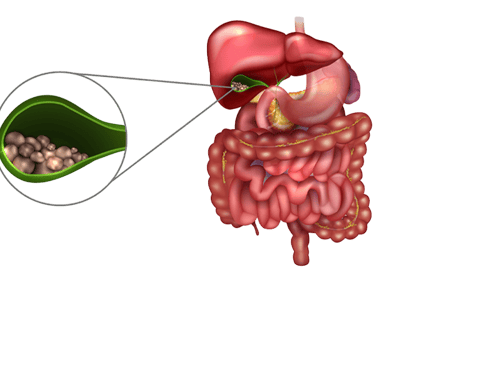

Cálculos biliares são pequenas “pedras” que se formam dentro da vesícula biliar — um órgão localizado abaixo do fígado e responsável por armazenar a bile, um líquido que ajuda na digestão das gorduras. Essas pedras podem ter composição variada, sendo a maioria formada por colesterol. Em alguns casos, estão associadas a infecções ou alterações metabólicas.

A relação anatômica entre vesícula, via biliar e pâncreas. Um cálculo de vesícula pode migrar por entre essas estruturas, provocando as complicações da doença

A vesícula biliar pode acumular cálculos, na sua maioria formados por colesterol